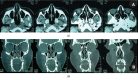

Leiomyomas are rare benign tumors that grow in the tunica media of smooth muscle cells. Leiomyomas occur most frequently in the uterus or gastrointestinal tract and only very rarely in the area of the cheek. This study reports on a rare case of a leiomyoma in the cheek of a 43-year-old woman, who presented with a well-circumscribed, asymptomatic, mobile swelling in the right cheek. This swelling was slightly purplish in color and measured approximately 4 cm × 3 cm. Surgical excision was the treatment of choice, and the diagnosis was based on histopathological and immunohistochemical stains, which were positive for actin and desmin and negative for AE1/AE3, CD34, and S100. The patient's follow-up, two years later, showed no recurrence, and she has been asymptomatic since the surgery.